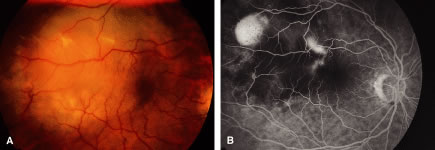

Metastatic cancer to the optic disc is rare (4.5% intraocular metastases).29 The optic disc is usually affected by direct extension of an adjacent choroidal metastatic tumor that infiltrates the optic disc (Fig. 3). Occasionally, tumor emboli enter the optic disc by hematogenous or intrathecal invasion (meningeal carcinomatosis). There is an adjacent juxtapapillary choroidal lesion in 74% of eyes.29 The associated findings include optic disc edema, venous stasis, an afferent pupillary defect, and less commonly hemorrhage or obstruction of a retinal artery or vein.8,29 The optic disc appears to be edematous, hyperemic, or atrophic in patients with meningeal carcinomatosis involving the optic nerve sheath.2,10,29 Most cases are from breast, lung, or an unknown primary malignancy. The differential diagnosis includes papilledema, optic neuritis, granuloma, optic disc drusen, and capillary hemangioma.8